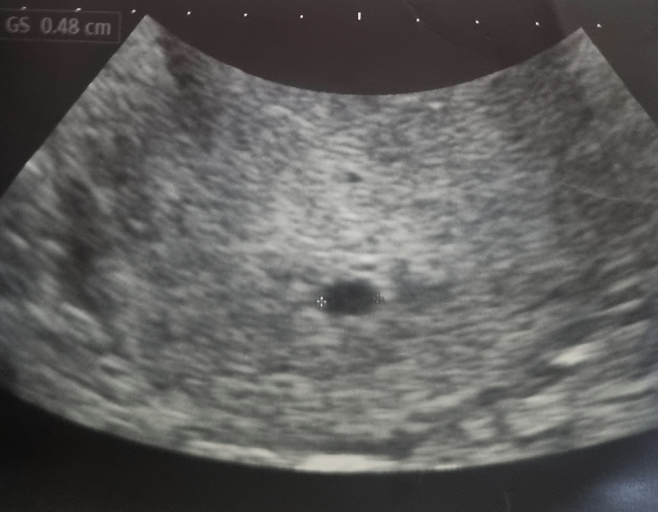

병원 초음파로 아기집이 확인되는 시기는 보통 임신 5~6주, 심장 박동은 7~8주 전후입니다.따라서 정확한 확인을 위해서는 일정 기간 기다리는 것이 중요합니다.